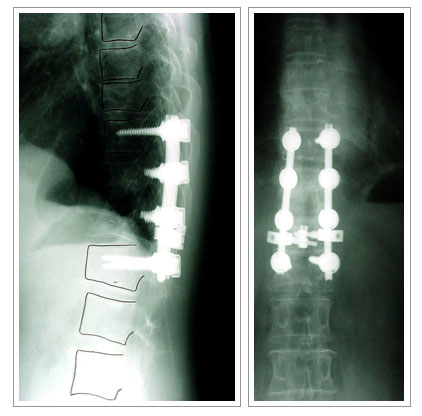

- 화농성 척추염

가장 흔한 균으로 황색포도상구균(박테리아)에 의해 염증이 생기는

질환이며 급성기에는 발열 등 화농성 질환에 따르는 증세와 함께 국소적인 등 허리의 통증이

심하며 내버려두면 패혈증으로 발전해 사망할 수도 있습니다. 초기에는 결핵성척추염과 구별이

- 비수술적 치료 ; 항생제 + 환부고정(보조기)

- 수술적 치료 ; 전방접근법을 통한 농양 및 변연 절제술, 척추골재건 및 변형교정을

위한

자가 골이식과 임플란트 내고정술 |